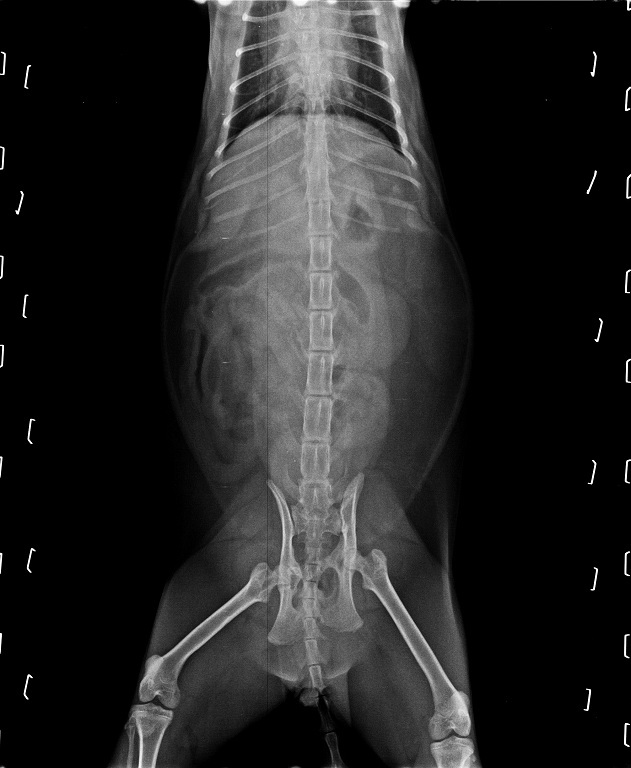

小樹在住院期間做了非常詳盡的各項檢查,

包括全套血檢、心絲蟲檢測,

並且做了先前沒做過的愛滋白血快篩,

也拍了X光照片確認小樹是否有吞下不尋常的異物。